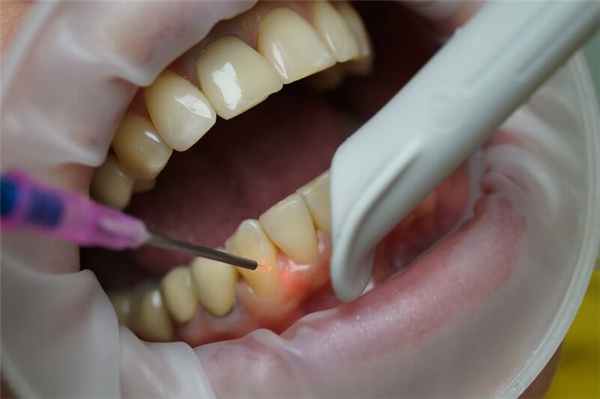

- цистотомия - самый простой и наименее травматичный метод: в области кисты на десне проводится надрез, через который устраняется содержимое кисты